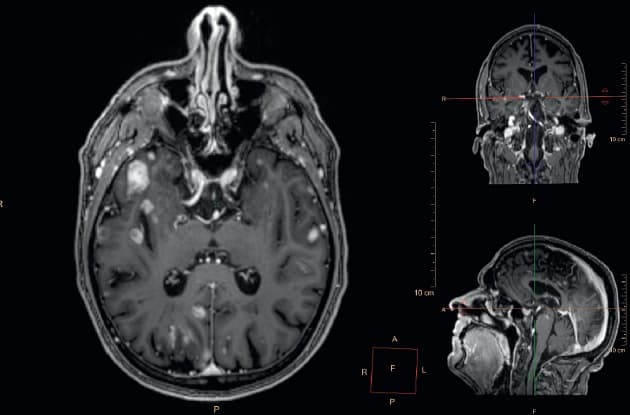

© MR-skanningsbilleder af hjernemetastaser fra et melanom.